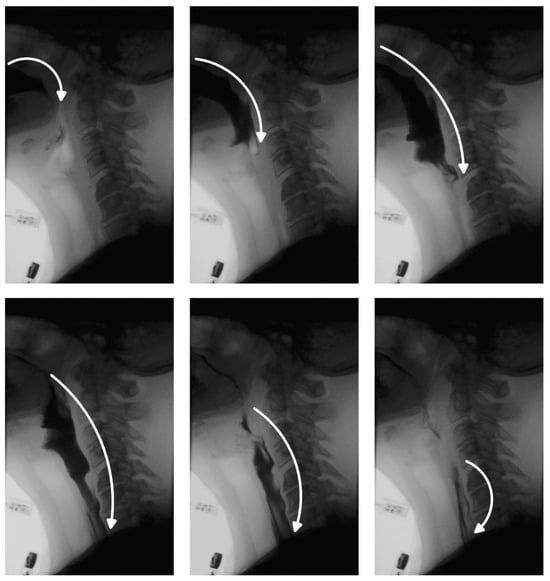

Figure 6 illustrates how flipping alters the spatial relationship between image content and positional encoding. This misalignment introduces inconsistencies that can confuse the model during training. At inference time, such discrepancies led to bolus detection failures in our experiments.

Figure 6. Visualization of how geometric augmentations (here, flipping) introduce inconsistencies between visual features and positional encoding. The same anatomical region may be associated with different positional cues, and conversely, the same positional coordinates may correspond to different anatomical content. This mismatch can confuse the model during training and contribute to segmentation failures at inference time. We use “RGB” notation here to represent pixel intensity values for visualization purposes only.